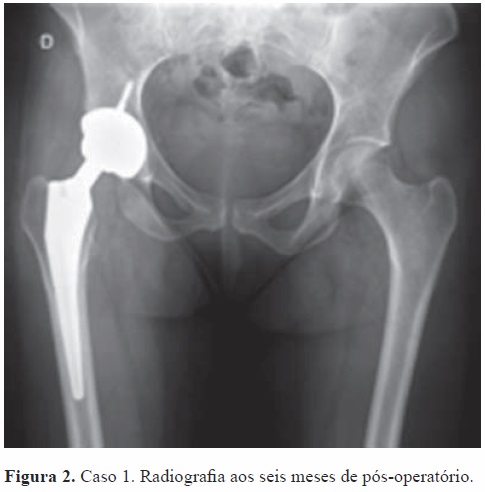

Foi internada por Obstetrícia para realização de cesariana de urgência. Uma semana depois a doente foi submetida a artroplastia total da anca direita não cimentada, cerâmica/cerâmica (Figura 2).

Neste momento tem seis meses de pós-operatório, encontra-se sem queixas álgicas e deambula sem apoio externo na marcha.

Relativamente aos casos apresentados: no caso 1 optou-se por realizar artroplastia total da anca direita, não cimentada, ao 7º dia pós parto. Na literatura consultada só encontramos referência a uma situação em que o tratamento da fratura consistiu na realização de artroplastia total da anca não havendo, porém, referência aos critérios que levaram a optar por essa estratégia cirúrgica.